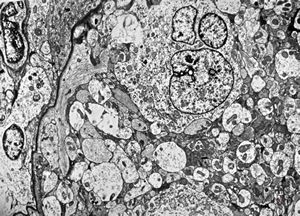

F,50y. | progressive multifocal leukoencephalopathy- viral particles in a glial cell